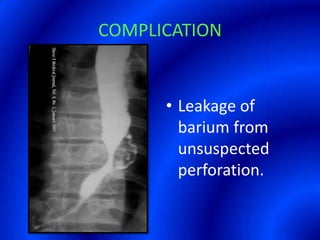

This document provides information about a barium swallow procedure. It begins with an introduction and overview of the embryology and anatomy of the pharynx and esophagus. It then describes the procedure itself, including preparation, technique, views obtained, and indications. Specific conditions that may be examined include pharyngeal and esophageal webs, foreign body impaction, scleroderma, dysphagia, mediastinal masses, and carcinoma. Diagrams are provided to illustrate normal anatomy and various pathological findings.